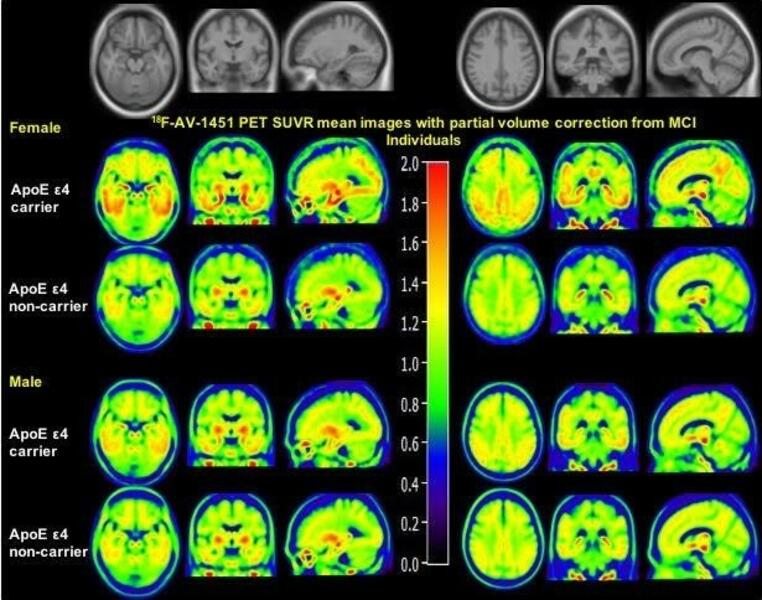

El análisis abarcó a 99 mujeres de entre 46 y 58 años y un grupo de comparación de 29 hombres de edad similar. Confirmó que las mujeres posmenopáusicas y perimenopáusicas (que inician la menopausia), en comparación con las mujeres premenopáusicas y los hombres, tenían un volumen de materia gris significativamente menor en áreas cerebrales como el hipocampo, el córtex entorrinal y las regiones del lóbulo temporal, muy afectadas por el Alzheimer.

Por el contrario, entre las mujeres, tener una mayor exposición a los estrógenos, según varios factores, se asoció con una mayor volumen de materia gris en ciertas áreas cerebrales. La mayor duración de la vida reproductiva, por ejemplo, se relacionó significativamente con una mayor volumen de materia gris en un grupo de regiones cercanas a la parte superior del cerebro, incluyendo el lóbulo parietal superior y el precuneus del hemisferio izquierdo.

Haber tenido más hijos se asoció significativamente con una mayor volumen de materia gris en los giros frontales inferiores y medios, y en los giros temporales medios e inferiores. Haber utilizado terapia hormonal sustitutiva se asoció a una mayor volumen de materia gris en la circunvolución frontal superior y en varias otras regiones cerebrales. Se sabe que todas estas regiones cerebrales se ven afectadas por el envejecimiento y el Alzheimer.